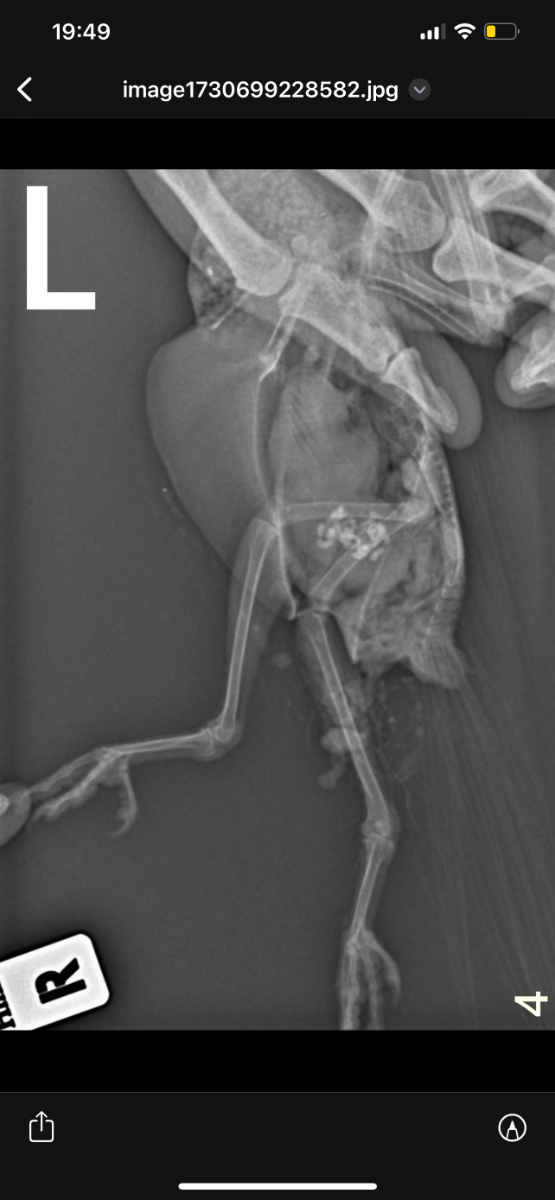

Здравствуйте, неделю назад возле автомобиля обнаружила голубя , лежал на левом боку и не мог встать. Я подумала что сбила машина, взяла его к себе. Съездили к орнитологу , он пощупал лапки , сказал возможно это связано с нервной системой , либо повреждена левая лапа. Голубь, взлетает без проблем. Но не упирается на лапы , теряет координацию и падает + постоянно вся попа в 💩. Кушает хорошо и пьет водичку самостоятельно. Сегодня смотрю , упирается на правую лапу , а левую вытягивает прямо назад.

На всякий случай купила витамины, добавляю по капельки в водичку. Голову не запрокидывает.  Фото рентгена прилагаю. Кто сталкивался с подобным ? Что может быть ?

Возможно есть повреждение бедренной кости- выбита или перелом головки.